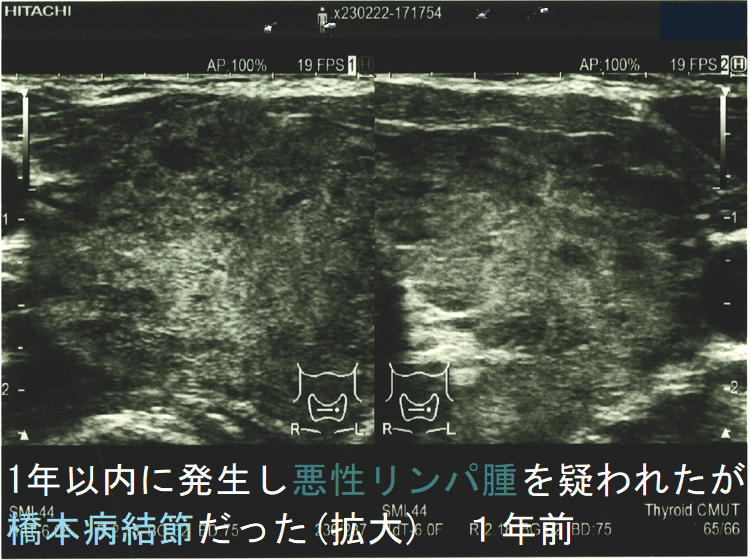

![1年以内に現れ悪性リンパ腫が疑われたが橋本病結節だった 1年前 (水平断)[拡大] 1年以内に現れ悪性リンパ腫が疑われたが橋本病結節だった 1年前 (水平断)[拡大]](../images/special/thyroid2/images20251130213537.png)

橋本病(慢性甲状腺炎)ではリンパ球浸潤に伴う炎症から濾胞細胞の好酸性変性[好酸性細胞(Hürthle細胞,ハーテル細胞)]・過形成、浮腫、線維化で結節性病変を形成[結節性橋本病(橋本病結節)]。病理学的に腺腫様甲状腺腫・腺腫様結節と同じで、橋本病(慢性甲状腺炎)を基盤とする腺腫様甲状腺腫・腺腫様結節。超音波(エコー)検査では内部が極めて低エコーのため甲状腺癌、甲状腺原発悪性リンパ腫と鑑別必要。細胞診では好酸性細胞、リンパ球集簇、炎症性多核巨細胞を認め、甲状腺乳頭癌ワルチン腫瘍型、通常型甲状腺乳頭癌・亜急性甲状腺炎と鑑別要。

橋本病(慢性甲状腺炎)では、リンパ球浸潤に伴う炎症から、濾胞細胞の好酸性変性・過形成、浮腫、線維化などの変化で結節性病変が形成されます[結節性橋本病(橋本病結節)]。病理学的には腺腫様甲状腺腫・腺腫様結節と同じ事で、橋本病(慢性甲状腺炎)を基盤とする腺腫様甲状腺腫・腺腫様結節になります。